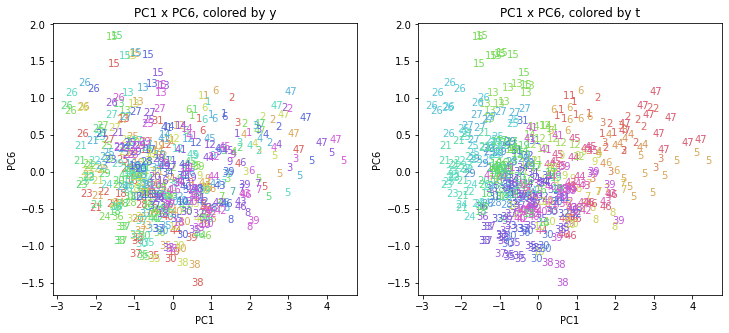

PCAの結果の第n主成分をPCnと表記します。

医療費データの場合と同様に、PCAの結果を見やすく表示するため、seabornのカラーパレットを使って、年月別、都道府県別に色分けして図示してみます(左側が年月別に色分け、右側が都道府県別に色分け)。PC1~PC8まで表示しました。

都道府県番号の表示

上の色分けだけでは都道府県が区別しにくいので、医療費データの場合と同様に、点の代わりに都道府県番号をプロットした図も描いておきます(色分けは上と同じ)。

医療費データの場合ほどはっきりとはしていませんが、PC2が概ね時間の経過を表す成分で、残りの成分が時点によって変わらない地域の特徴を表す成分となっているようです。

また、PC1×PC3を見ると、47沖縄が他の都道府県からかなり離れたところに位置しており、沖縄の地域差が際立っているのが分かります。これは、以前別の記事で年齢階級のない健診データでPCAを実行した場合と似た結果となっています。